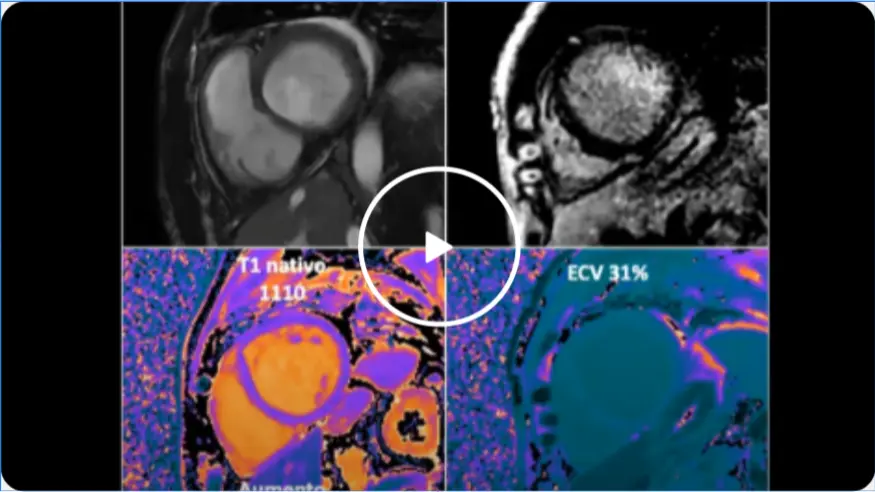

Ressonância com AI: impactos em produtividade e qualidade Clínica

Dr. Gustavo Simão